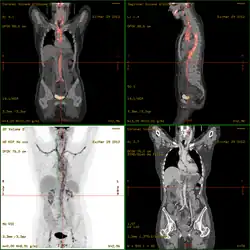

2-FDG wird in der PET für die Diagnose,[24] Staging (Stadienbestimmung), Therapieeinstellung und Therapiekontrolle verwendet. Man spricht in diesem Zusammenhang auch oft von der „FDG-PET“. 2-FDG ist als Diagnostikum eine außerordentlich nützliche und vielfach bewährte Verbindung. Die Anwendung hat einen rein diagnostischen Hintergrund. Genutzt wird dabei die bei der Paarvernichtung (Annihilation) von Positron und Elektron entstehende Vernichtungsstrahlung. Bei der Annihilation entstehen zwei hochenergetische Photonen, die eine Energie von 511 keV haben und in einem Winkel von 180 Grad zueinander, ausgesandt werden. Für die Therapie (Strahlentherapie, in diesem besonderen Fall würde man von einer Endoradiotherapie sprechen) sind die für die Diagnostik genutzten Gammaquanten nicht geeignet.

Für die FDG-PET gibt es drei Hauptindikationen für die Untersuchung von Patienten mit onkologischen Erkrankungen:[19] die Differenzierung zwischen benignen oder malignen (gutartig oder bösartig) Tumoren, das Tumorstaging bezüglich der Lymphknoten und Fernmetastasen sowie die Differenzierung Narbengewebe/vitales Tumorgewebe (Rezidiv, residueller Tumor). Die FDG-PET wird in der Onkologie zur Untersuchung von Lungenkrebs, dem kolorektalem Karzinom, Speiseröhrenkrebs, Magenkrebs, Kopf-Hals-Karzinom, Gebärmutterhalskrebs, Eierstockkrebs, Brustkrebs, dem malignen Melanom und den meisten Arten von Lymphomen eingesetzt.[31] Insbesondere sehr langsam wachsende Tumoren weisen in der Regel keine wesentlich erhöhte FDG-Aufnahme aus. Eine FDG-PET-Untersuchung ist dann meist nur in Ausnahmefällen sinnvoll.[19] Dazu gehören Prostatakarzinome, differenzierte neuroendokrine Tumoren (z. B. Karzinoid), bronchoalveoläre Karzinome, niedrig maligne Non-Hodgkin-Lymphome, niedrig maligne Hirntumore (Astrozytom II, Oligodendrogliom II) und das Leberzellkarzinom (vor allem höher differenzierte Formen). Entzündungen bzw. Heilungen zeigen neben dem Tumorgewebe ebenfalls eine erhöhte Stoffwechselaktivität und somit eine erhöhte FDG-Aufnahme. Eine Untersuchung zur Differenzierung beispielsweise von Abszessen und Tumorgewebe, Sarkoidose, Bronchialkarzinomen usw., kann deshalb mit 2-FDG kaum sinnvoll durchgeführt werden.[19]

Im Fall des Ganzkörper-Scans auf der Suche nach Tumoren oder deren Metastasen wird eine Dosis von etwa 200 bis 400 MBq über eine isotonische Kochsalzlösung in eine Vene des Patienten injiziert. Über die Körperoberfläche des Patienten wird die zu applizierende Aktivitätsmenge errechnet. Die Zielgröße ist es dabei, etwa 210.000 Ereignisse pro Schicht im PET registrieren zu können.[19] Die empfohlene Maximaldosis einer FDG-Injektionslösung liegt bei 10 mg,[15] entsprechend 55 Mikromol.